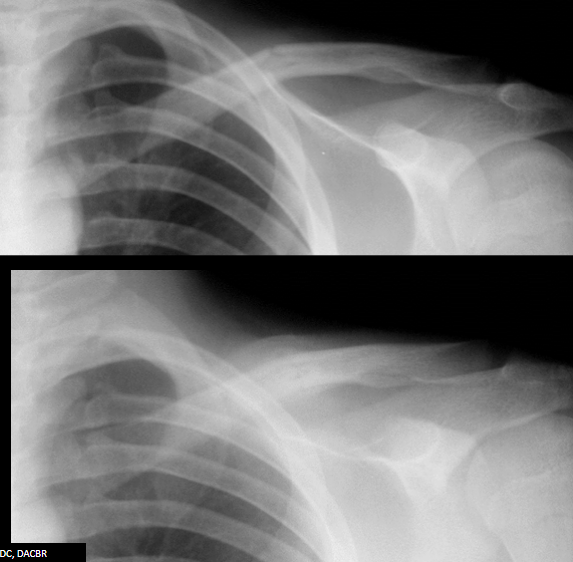

13

Q

What stage of fracture healing is the top picture in?

What stage is the bottom picture in?

A

Top: inflammatory

Bottom: reparative